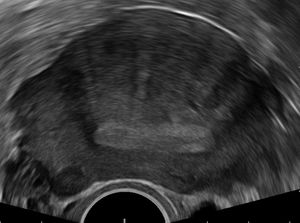

5. 1. 경질 초음파 검사 (TVUS)

경질 초음파 검사는 산부인과 증상 평가 초기에 일반적으로 사용되는 저렴하고 쉽게 구할 수 있는 영상 검사이다.[23] MRI와 마찬가지로 초음파 영상은 방사선을 사용하지 않아 골반과 여성 생식 기관 검사에 안전하다.[24] 전반적으로 경질 초음파 검사는 자궁선근증 진단에 대해 79%의 민감도와 85%의 특이도를 갖는 것으로 추정된다.[9]일반적인 경질 초음파 소견은 2015년 유럽 MUSA 그룹에 의해 정의되었으며,[25] 2022년 MUSA 그룹에 의해 다시 정의되었다.[26] 초음파 특성은 직접적 특징과 간접적 특징으로 나눌 수 있다.

직접적 특징:

- 근층 낭종 - 자궁의 평활근 내의 액체 주머니

- 고에코 섬 - 일반적으로 근층 내의 흰색 자궁내막 섬

- 에코성 자궁내막 하선과 싹 - 일반적으로 자궁내막에 부착되어 근층으로 돌출된 흰색 선과 혹

간접적 특징:

- 둥글고, 확대되고, 비대칭적인 자궁

- 부채꼴 그림자 - 선형 그림자를 가진 자궁 근종과 구별

- 전/후벽 비대칭

- 이동 혈관 - 근층 내의 작은 혈관의 확산

- 불규칙하거나 중단된 접합부 - 자궁내막과 근층 사이의 경계선

경질 초음파 검사 동안 파워 도플러 또는 도플러 초음파 기능을 사용하여 자궁선근종을 자궁 근종과 구별하는 데 도움이 될 수 있다.[23][27][28] 이는 자궁 근종이 일반적으로 근종의 캡슐을 둘러싸는 혈관을 가지고 있기 때문이다. 반대로, 자궁선근종은 병변 내에 광범위한 혈관이 있다는 특징이 있다.[23] 도플러 초음파는 또한 근층 낭종 내의 정적 액체를 혈관 내에서 흐르는 혈액과 구별하는 데 사용된다.[23]

접합부(JZ), 즉 자궁내막-근층 경계면의 작고 뚜렷한 호르몬 의존적 영역은 3차원 경질 초음파(3D TVUS) 및 MRI로 평가할 수 있다. 자궁선근증의 특징은 접합부의 파괴, 비후, 비대 또는 침윤이다.[19] 접합부의 실제 조직학에 대한 합의는 없으며, 최근 검토에 따르면 초음파, MRI 및 조직학 모두 접합부를 다르게 정의하고 설명한다는 것을 보여주었다.[29]